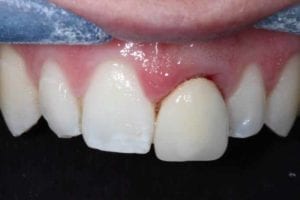

Upper incisor Replacement with Partial Extraction

The upper left lateral incisor was broken and beyond repair, in order to prevent shrinkage of the gum (which can sometimes happen after tooth removal). A small part of the root was left in by undertaking a partial extraction (Socket shield), placing a dental implant and then a crown to fill the gap. This innovative treatment maintains a small piece of the root next to the dental implant (under the gum) so that the gum doesn’t shrink back and a long crown would have to be made to fill the space. This was especially important here as the patient’s gum line is visible when she smiles.